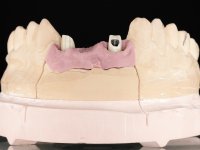

The surgical implant exposure and the healing screw placement proved to be a negative surprise regarding its position. Since the proposed removal of the implant was refused, we advanced to its provisional rehabilitation. An open tray impression technique was done, and a screwed abutment with a coronal and gingival component and an acrylic crown were made in the laboratory, using these two components. The provisional crown was placed in the mouth until a final decision was made. Six years passed before the patient returned to the clinic with an abscess on tooth 1.1. The choice to remove teeth 1.1 and 2.2 was made, to create a provisional 3-element bridge with a net to be adhered to the adjacent teeth. Surgery was planned and performed, placing the two implants at the site of 1.1 and 2.2, and the implant at the 2.1 site was cut with the objective of submerging it, while adequate tissue regeneration was performed (Surgical Work performed By Dr. Manuel Neves). During osseointegration, the patient used the fixed provisional bridge. A first impression was made for confection of a zirconia screwed provisional bridge, which worked the soft tissues for twelve weeks. The definitive impression was made with the individualisation of custom impression copings. Final rehabilitation was done with ceramized abutments, and also a bridge with zirconia infrastructure and ceramic cover. Due to the inclination of the implant placed at the site of tooth 1.1, the bridge required cemented fixation.